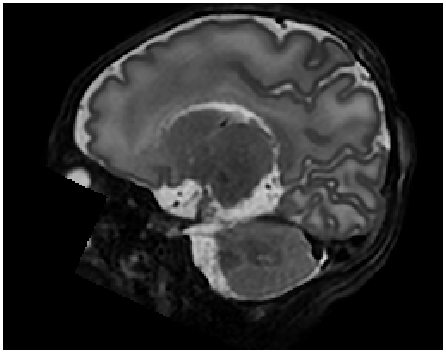

VI-D Semantic Interpolation of Adult Brain MRI

Upsampling performance of the proposed method was also evaluated using T1-weighted (T1w) adult brain MRIs of the OASIS project ([40]). The images with isotropic resolution of 1.01.01.0×\times1.01.01.0×1.0 mm3absentsuperscripttimes1.0millimeter3\times$1.0\text{\,}\mathrm{mm}$^{3} served as ground truth high-resolution (HR) images.

VI-D2 Results

Slice Synthesis: Qualitative evaluation of proposed method on adult brain MRI with reveals that synthesized slices constitute a smooth anatomical transition between neighboring slices. The proposed method is able to bridge large anatomical variations between adjacent slices. These findings are depicted in Figure 12.

Comparison With Conventional Interpolation Method: Qualitative comparison of generated axial brain MRI slices between cubic B-spline interpolation and proposed approach shown in Figure 13 reveals that the proposed method can synthesize excluded axial slices with higher image quality than conventional interpolation method. Moreover, visual inspection of coronal and sagittal slices shown in Figure 13 conveys that images generated by cubic B-spline interpolation more frequently suffer from aliasing artifacts than images generated by our proposed method.

In line with results reported for cardiac cine and neonatal brain MRI in Sections VI-B and VI-C, respectively, quantitative evaluation in terms of SSIM, PSNR, and VIF depicted in Figure 14 corroborate the qualitative findings. Measures were computed on sagittal slices through volume. The proposed method outperformed cubic B-spline interpolation and the differences are statistically significant (p<0.0001𝑝0.0001p<0.0001) in terms of SSIM and PSNR for all upsampling factors (K{2,3,4,5,6}𝐾23456K\in\{2,3,4,5,6\}).